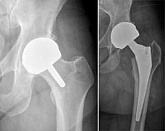

Hüftendoprothetik

In den späten Stadien der Arthrose des Hüftgelenks, mediale Frakturen des Schenkelhalses in der älteren Altersgruppe, ist die einzige Möglichkeit, sich zu erholen, das betroffene Gelenk durch eine künstliche Gelenkarthroplastik zu ersetzen.

Diese Methode ermöglicht es Ihnen, die Gliedmaße, das volle Volumen der Bewegungen im betroffenen Gelenk, zurückzugeben, um von ständigem Schmerz und Knirschen während der Bewegungen zu sparen und folglich den Patienten zu einem vollen aktiven Leben zurückzubringen.

Im Folgenden werden Röntgenaufnahmen und Fotografien vorgestellt, die das Ausmaß der Bewegung im betroffenen Gelenk vor und nach der Operation zeigen.